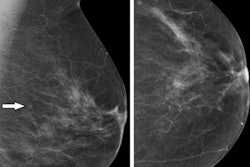

While digital mammography remains the gold standard for breast cancer screening and detection, some have expressed concern over the use of ionizing radiation in breast tissue.

While autofilter has been the go-to option for screening mammography, recent research on phantom models suggests that there are tradeoffs in dosage and image quality when using either auto or manual controls for varying levels of breast thickness.